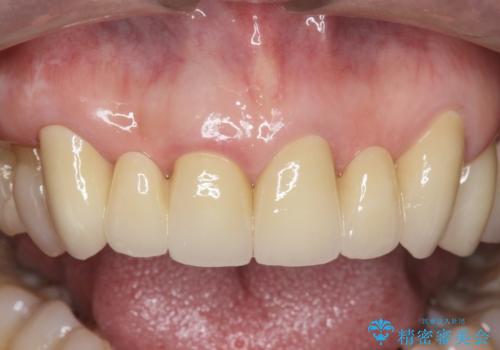

不自然な前歯ブリッジ ジルコニアブリッジによるやり替え

丁寧に現在装着されているブリッジを除去後、精度の高いジルコニアブリッジで審美性の改善を計画します。

前歯に限らず拡大鏡を用いた精密な形成・シリコンを用いた精度の高い印象を徹底することで治療全体の質を高め、審美性だけでなく長期的な予後を期待することができます。